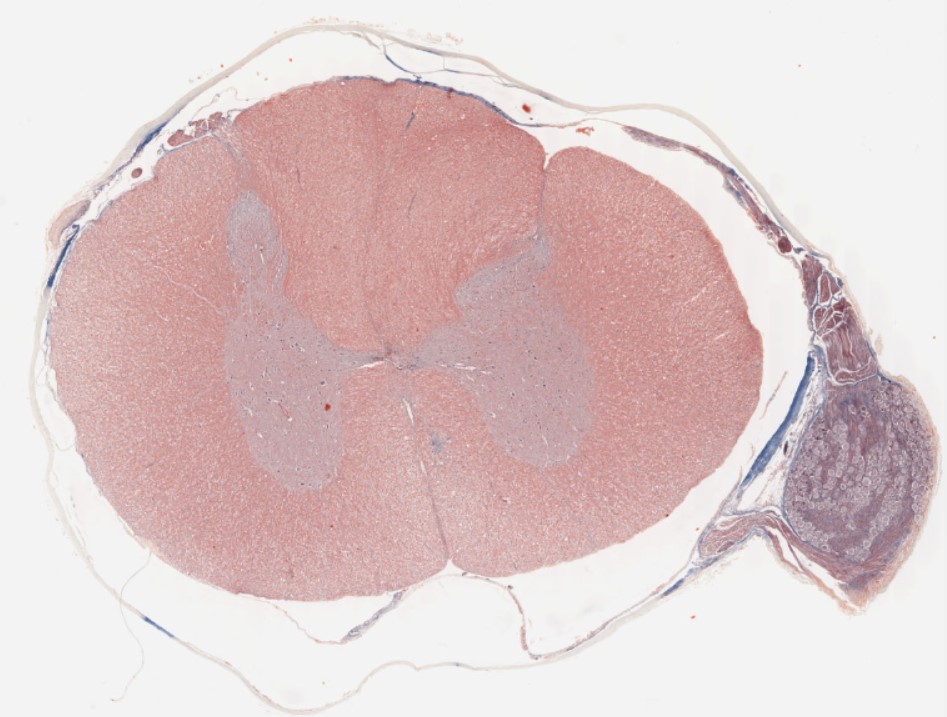

Image Link: https://histologyslides.med.umich.edu/Histology/Basic%20Tissues/Nervous%20Tissue/065-1N_HISTO_40x.htm